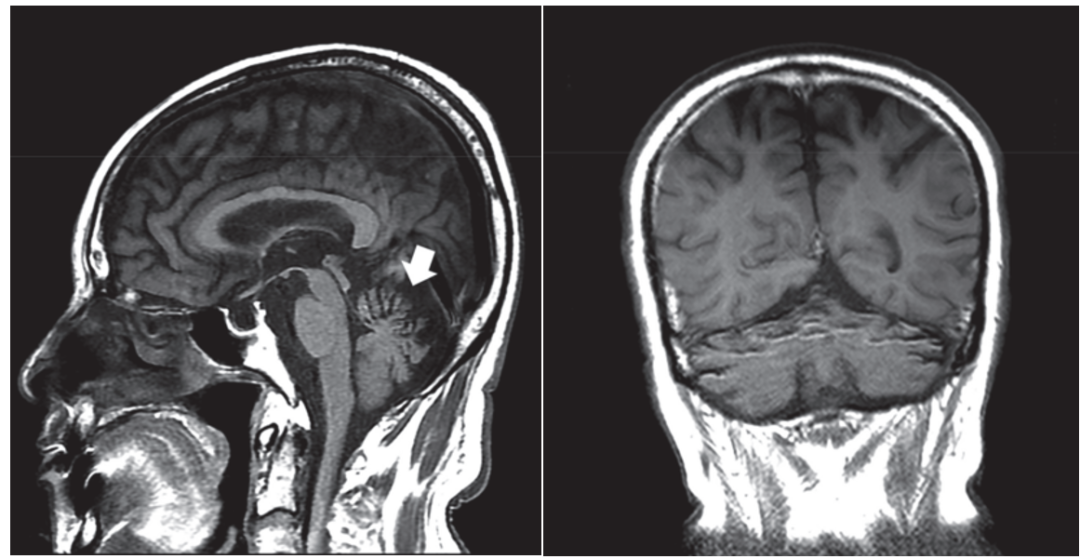

小脑变性

以小脑蚓部萎缩为主,环池、小脑上池、枕大池扩大,可合并大脑萎缩,主要的病理改变为小脑蚓部皮质变性。临床表现为共济失调、眼球震颤、言语缓慢、行走不稳。

颅脑MRI示小脑萎缩

尤其是在小脑蚓部和半球的的前部